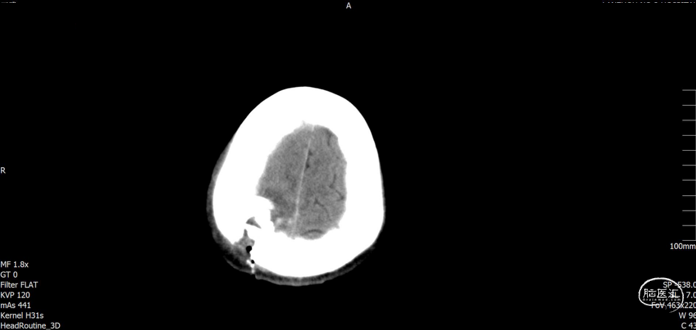

术后随访

术后CT

![]()